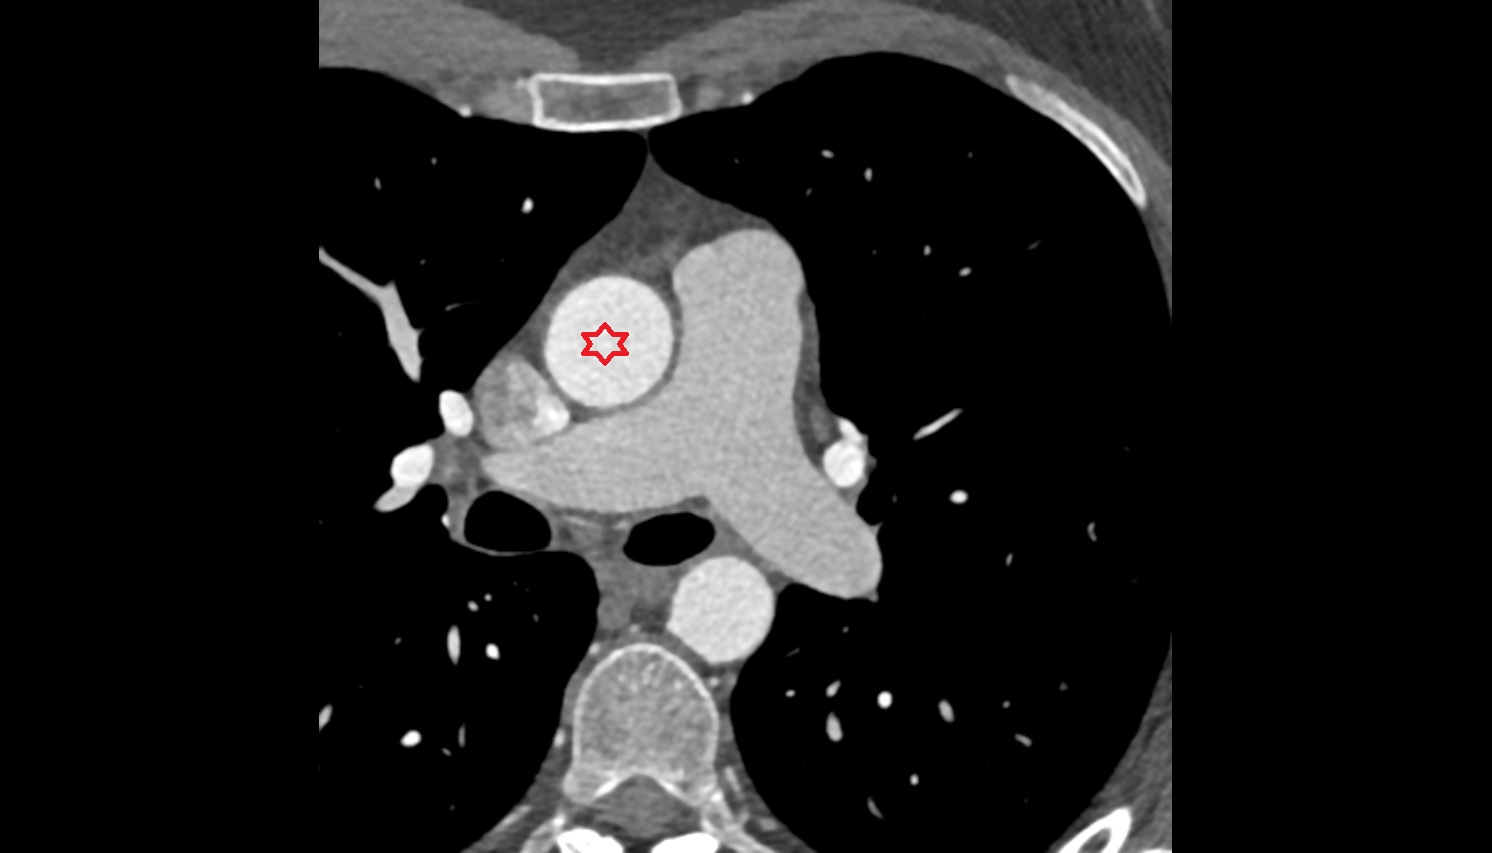

- Pericardium

- Heart

- Aortic root

- Ascending aorta